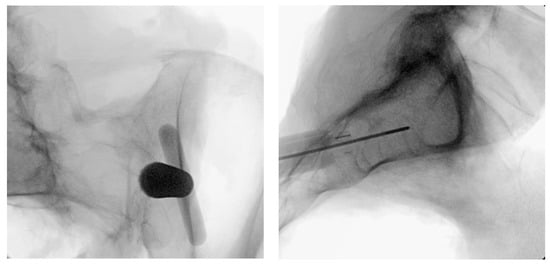

3.3.7. Docking Washer Introduction

3.3.8. Implant Insertion

3.3.9. Final Implant Placement